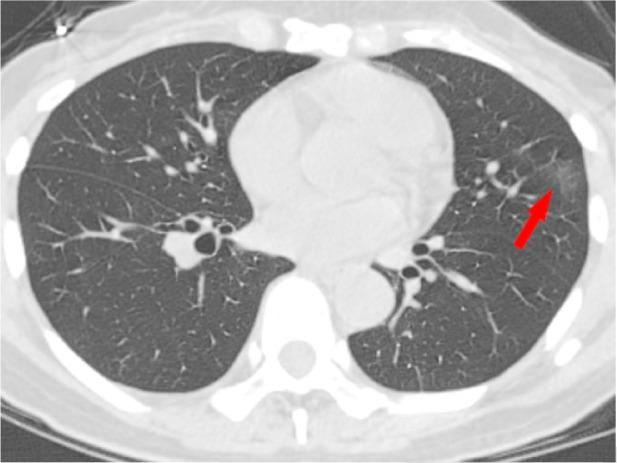

In December 2019, an outbreak of severe acute respiratory syndrome coronavirus 2 infection occurred in Wuhan, Hubei Province, China, and spread across China and beyond. On February 12, 2020, the World Health Organization officially named the disease caused by the novel coronavirus as coronavirus disease 2019 (COVID-19). Because most patients infected with COVID-19 had pneumonia and characteristic CT imaging patterns, radiologic examinations have become vital in early diagnosis and the assessment of disease course. To date, CT findings have been recommended as major evidence for clinical diagnosis of COVID-19 in Hubei, China. This review focuses on the etiology, epidemiology, and clinical symptoms of COVID-19 while highlighting the role of chest CT in prevention and disease control.

2019 年 12 月,中国湖北省武汉市发生了严重急性呼吸综合征冠状病毒 2 型感染的爆发,并在中国乃至全球蔓延。2020 年 2 月 12 日,世界卫生组织正式将由新型冠状病毒引起的疾病命名为 2019 冠状病毒病(COVID-19)。由于大多数感染 COVID-19 的患者都患有肺炎和特征性的 CT 影像学模式,放射学检查在早期诊断和疾病过程评估中变得至关重要。迄今为止,CT 检查结果已被推荐为中国湖北省 COVID-19 临床诊断的主要依据。本综述重点介绍了 COVID-19 的病因、流行病学和临床症状,同时强调了胸部 CT 在预防和疾病控制中的作用。